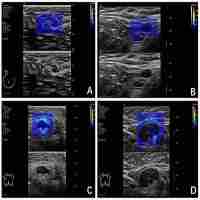

Quantitative shear wave elastography in the evaluation of breast cancer metastatic axillary lymph nodes

| Abstract | Poster: "ECR 2016 / C-0494 / Quantitative shear wave elastography in the evaluation of breast cancer metastatic axillary lymph nodes" by: "Y. Kabin1, V. V. Kapustin2, N. Smekhov3; 1Moscow region/RU, 2Moscow Oblast/RU, 3Moscow/RU" |